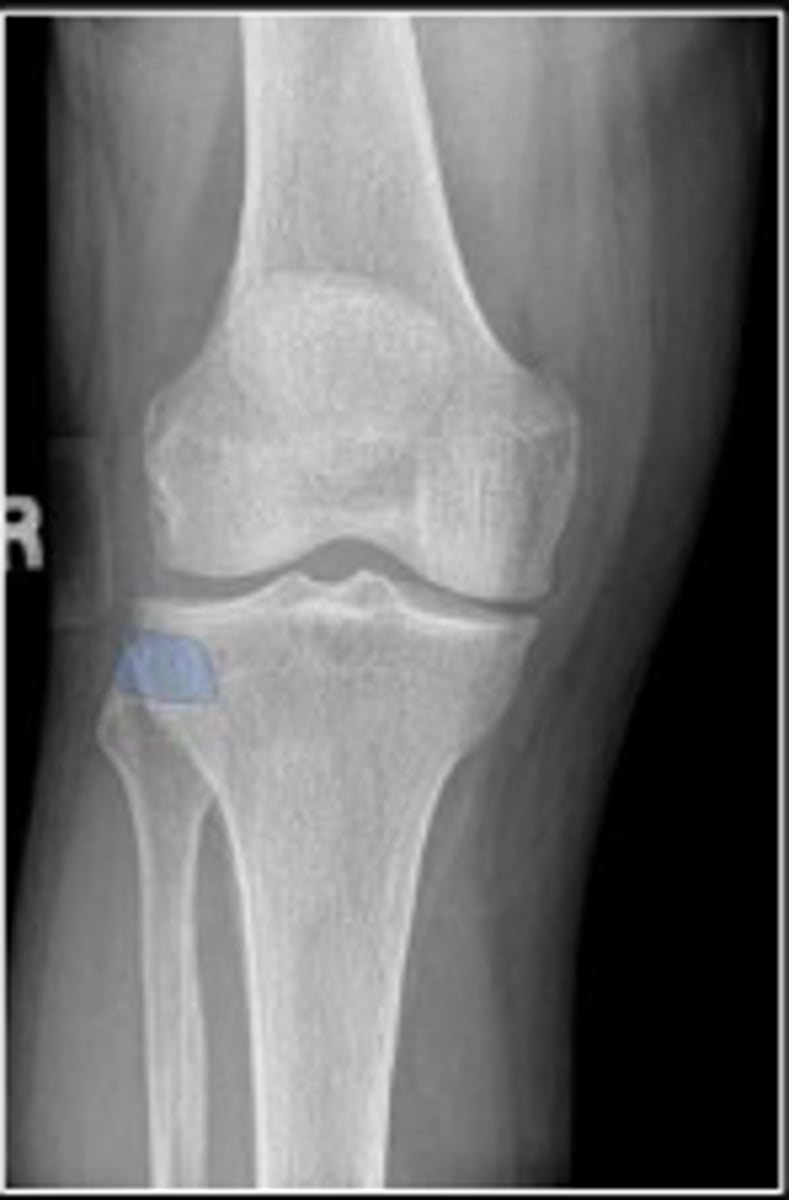

Right internal oblique knee

What is the name of the radiographic view?

Neck of the fibula

What are the blue arrows pointing to?

Ludloff's space/triangle

What are the red arrows pointing to?